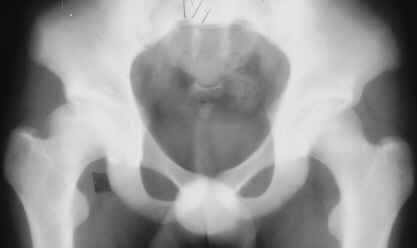

11 yrs 3 mos, , 12 yrs, 13 yrs 8 mos , 17 yrs , 18 yrs.

At 28 years of age, he had been having increasing pain in his right hip. He had a limp when he was tired. Positive Trendelenburg's sign was observed on the right. Internal rotation was limited to 25 degrees. All other motions were normal. X-ray showed cystic change. At the 29 years of age, he underwent bone graft of the right femoral head for degenerative cyst. At 35 years of age, only internal rotation was limited to 20 degrees. He still had pain in his hip that relates primarily to weather or to excessive walking. Only internal rotation was limited to 20 degrees. He had hip pain at the extremes of flexion and internal rotation. X-ray showed the progression of the cystic change. CT which was performed because of the question of loose bodies in the hip did not seem likely that the densities were actually in the hip joint. The antero-medial location of the cysts facing the anterior margin of the acetabulum was well depicted in CT.

28 yrs, 29 yrs, 30 yrs, 35 yrs .